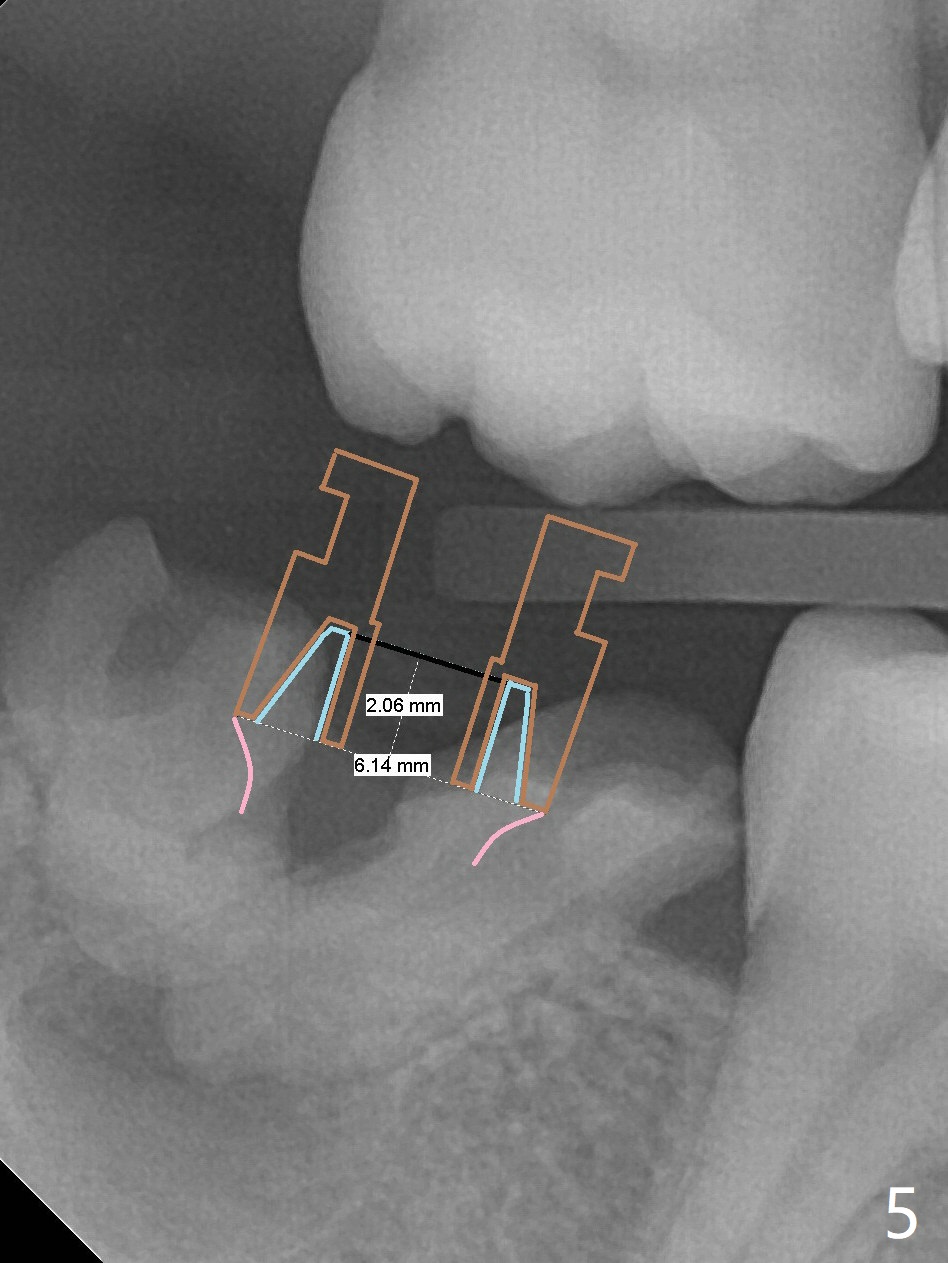

A 39-year-old man finishes orthodontic treatment without intrusion of the upper 2nd molar (Fig.1). He is reluctant for mini-implant placement for intrusion. After extraction of the tooth #31 with periapical radiolucency (Fig.2 *), a 5x11(4) mm Magicore will be placed with guide (Fig.3). Following osteointegration (Fig.4), a burn out core is going to be placed (Fig.5 brown, inside metal, outside plastic). With proper height adjustment, a provisional is fabricated around the core with acrylic (Fig.6 white). If the provisional keeps breaking down under occlusion, the case will be sent to lab for a screw retained crown with unfinished rough occlusal surface so that a thin layer restoration material able to be laid chair-side (acrylic or suction down material). Over time, the opposing tooth will be intruded (Fig.7 arrow).